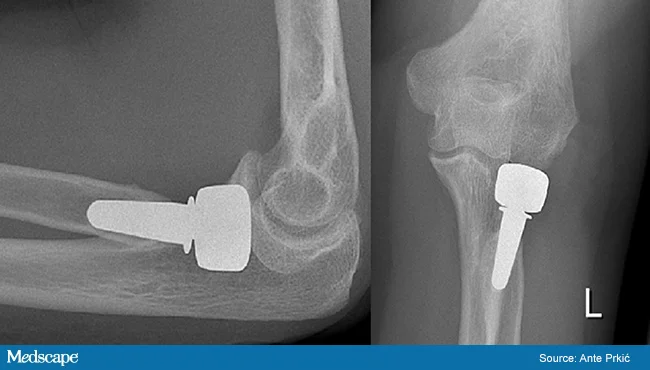

Fracture Distal Humerus

- Treated by open anatomical reduction and internal fixation by plates and screws

- Early mobilization to prevent elbow stiffness